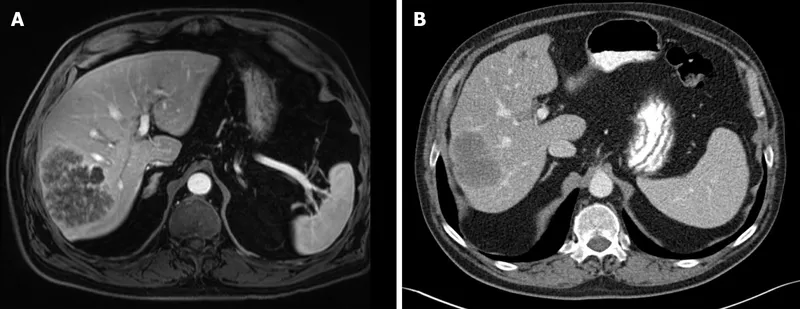

- MRI: Brain, liver, bone specifics.

- Liver: Most common for CRC; aim for ≥1 cm margin.

⭐ For colorectal liver metastases, 5-year survival after complete R0 resection can reach 40-50% in appropriately selected patients.